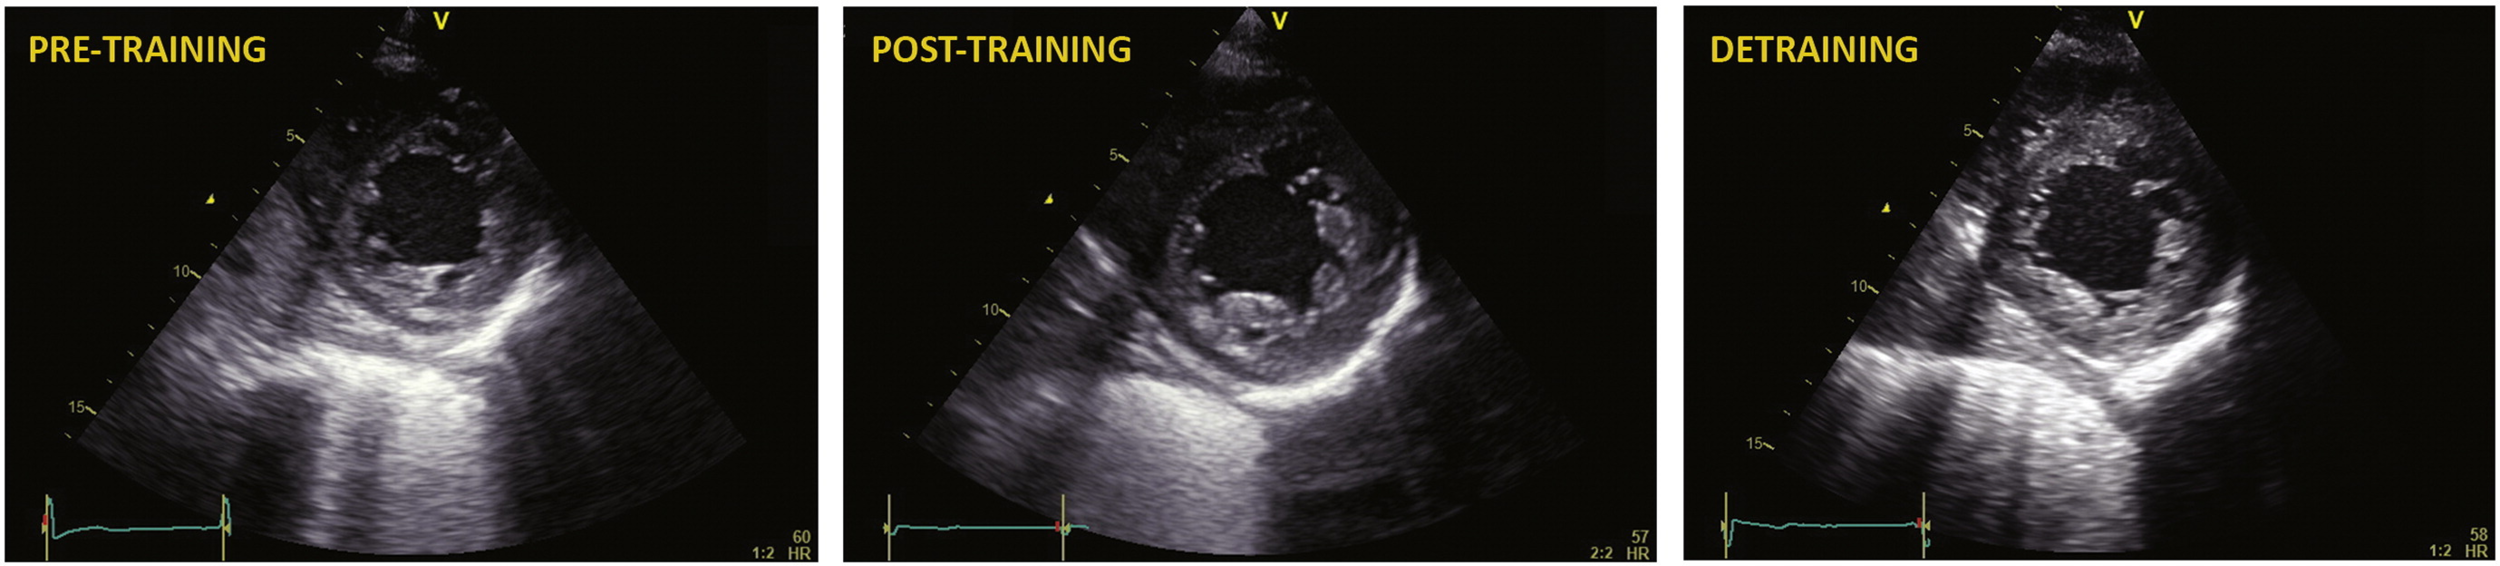

Mimic - Hypertrabeculation

• One study showed 18% of athletes have an increased LV trabeculation and 8% fulfilling the conventional criteria for LVNC

• Especially in African/Afro-Carribean athletes

• Longitudinal study needed